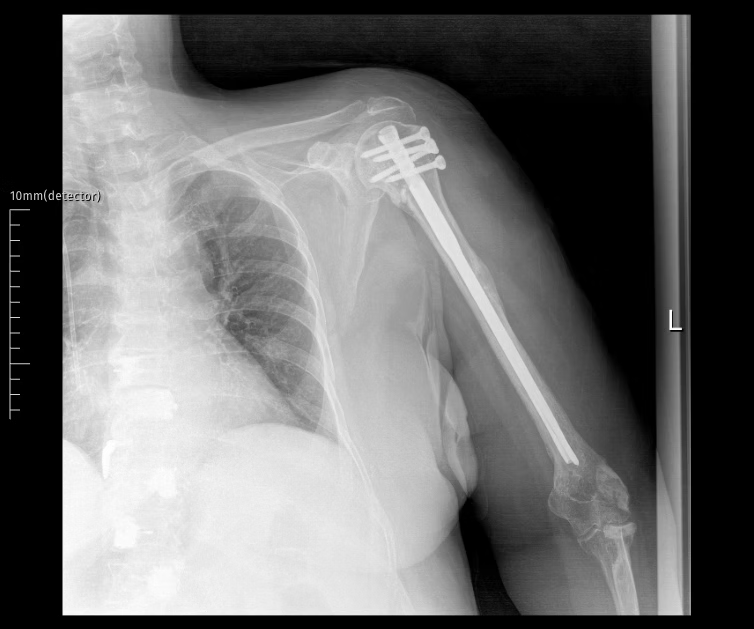

Surgical Techniques